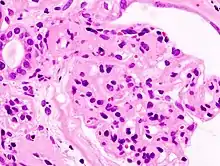

| Microscopic image of diabetic glomerulosclerosis, the main cause of nephrotic syndrome in adults. | |

- Focal segmental glomerulosclerosis (FSGS): is the most common cause of nephrotic syndrome in adults.[22] It is characterized by the appearance of tissue scarring in the glomeruli. The term focal is used as some of the glomeruli have scars, while others appear intact; the term segmental refers to the fact that only part of the glomerulus is damaged.